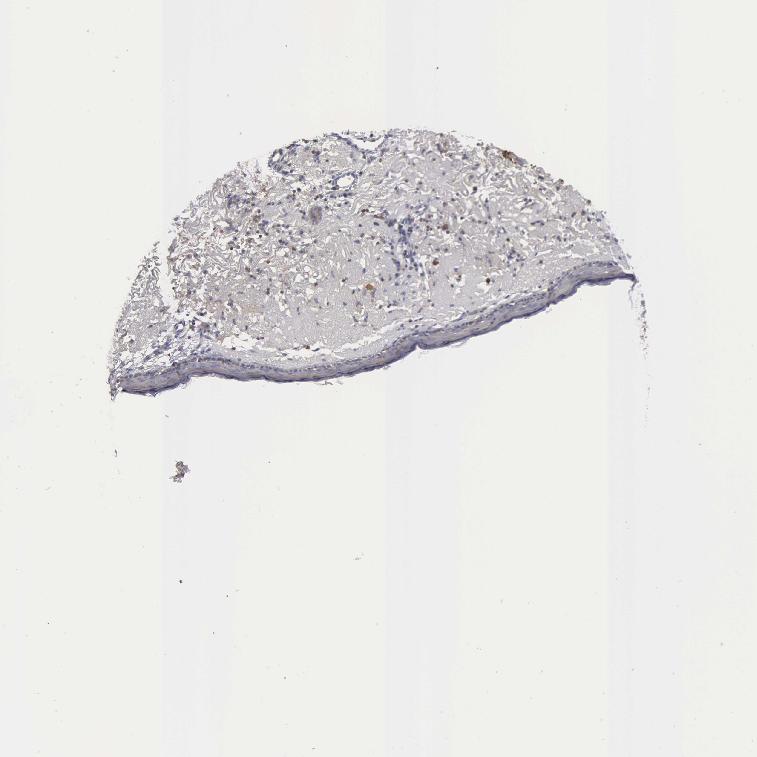

SKIN 1 - Antibody stainingi

Antibody staining in the annotated cell types in the current human tissue is reported as not detected, low, medium, or high, based on conventional immunohistochemistry profiling in selected tissues. This score is based on the combination of the staining intensity and fraction of stained cells.

Each image is clickable and will lead to virtual microscopy that enables deeper exploration of all samples and also displays staining intensity scores, fraction scores and subcellular localization as well as patient and tissue information for each sample.

Antibody HPA000247Antibody HPA000834

Langerhans LowNot detected

Fibroblasts LowNot detected

Keratinocytes LowNot detected

Melanocytes LowLow